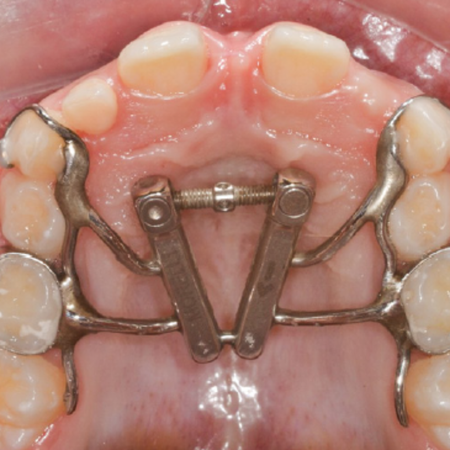

Objetivo: Comparar a abertura da sutura palatina mediana após a expansão rápida da maxila realizada com o expansor maxilar com abertura diferencial e com o expansor em leque. Métodos: Expansão rápida da maxila foi realizada com o expansor maxilar com abertura diferencial (n=12; 8 do sexo feminino, 4 do masculino; média de idade de 7,75 anos) e com o expansor em leque (n=12; 8 do sexo feminino, 4 do sexo masculino; média de idade de 8,08 anos). Tomografias computadorizadas de feixe...